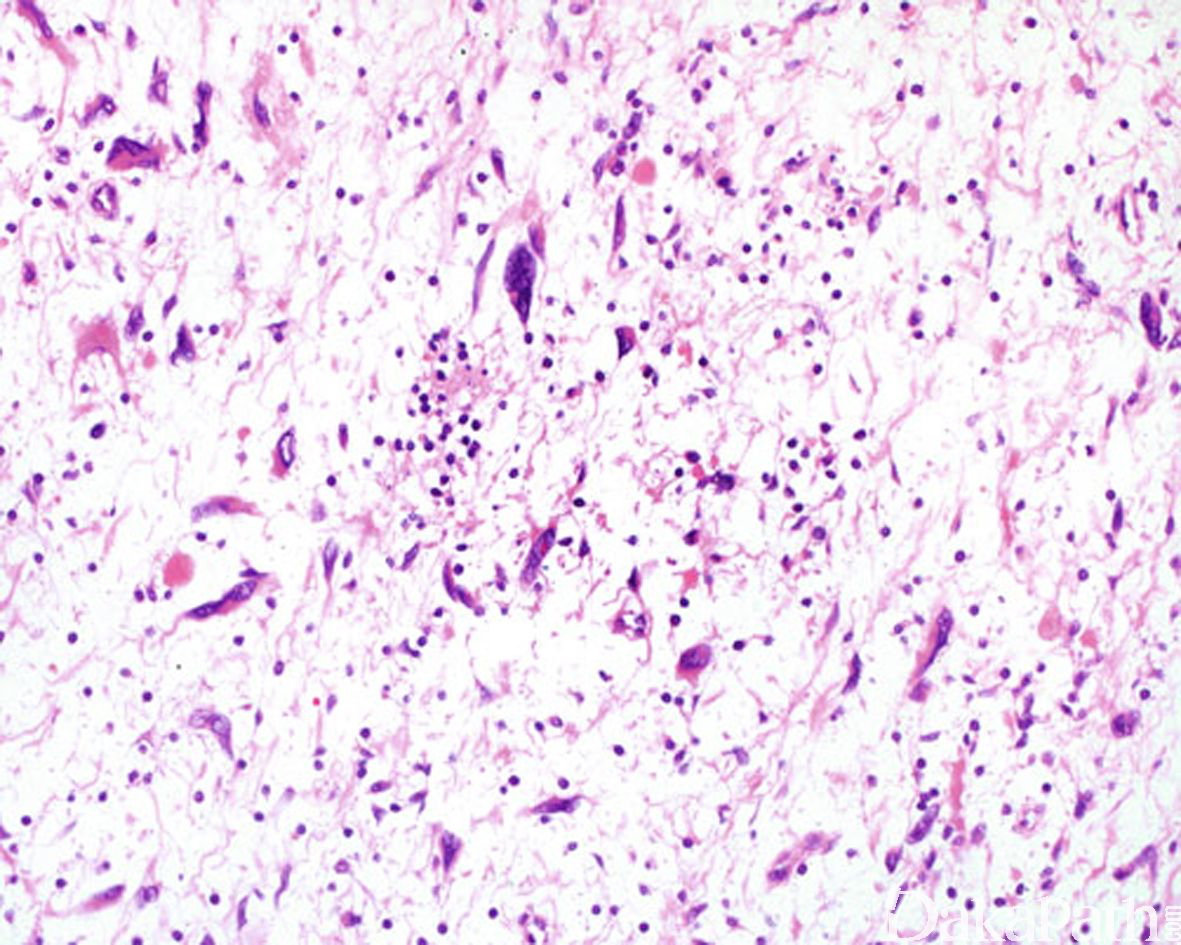

神经纤维瘤是良性周围神经鞘膜肿瘤,由施万细胞、纤维细胞母及少量的轴突、神经束膜细胞共同构成。

发病部位: 任何年龄均可受累,但最常见于年轻成人; 通常发生于全身的皮肤或皮下组织;大体表现为界清楚的纺锤形病变,常与神经干有关;切面质硬、灰白色;